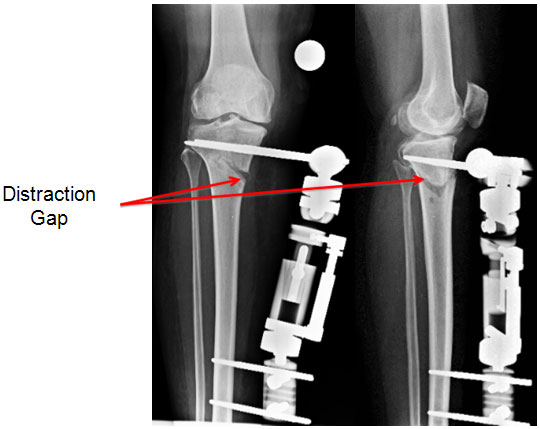

| 2 weeks post surgery |

| The gap at the osteotomy increases as distraction goes on, changing the angle with it. |